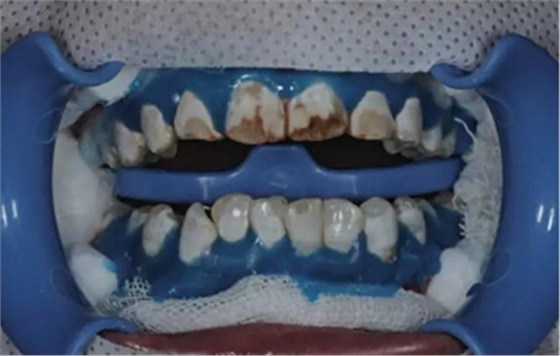

首先, 應(yīng)清潔牙齒或者由您的私人牙醫(yī)為您處理.應(yīng)用橡皮障之后 (Fig. 2),

應(yīng)用icon酸蝕劑酸蝕唇面2分鐘(Fig. 3).

由于最初的酸蝕結(jié)果并不令人滿意,因此我們重復(fù)酸蝕步驟. 利用乙醇干燥之后,可以看到顏色的改變。但是酸蝕結(jié)果還是不滿意,因此我們進(jìn)行了第三次酸蝕。在每一次酸蝕之后, 都應(yīng)將酸蝕劑徹底沖洗干凈然后用icon干燥劑進(jìn)行干燥 (Fig. 4).